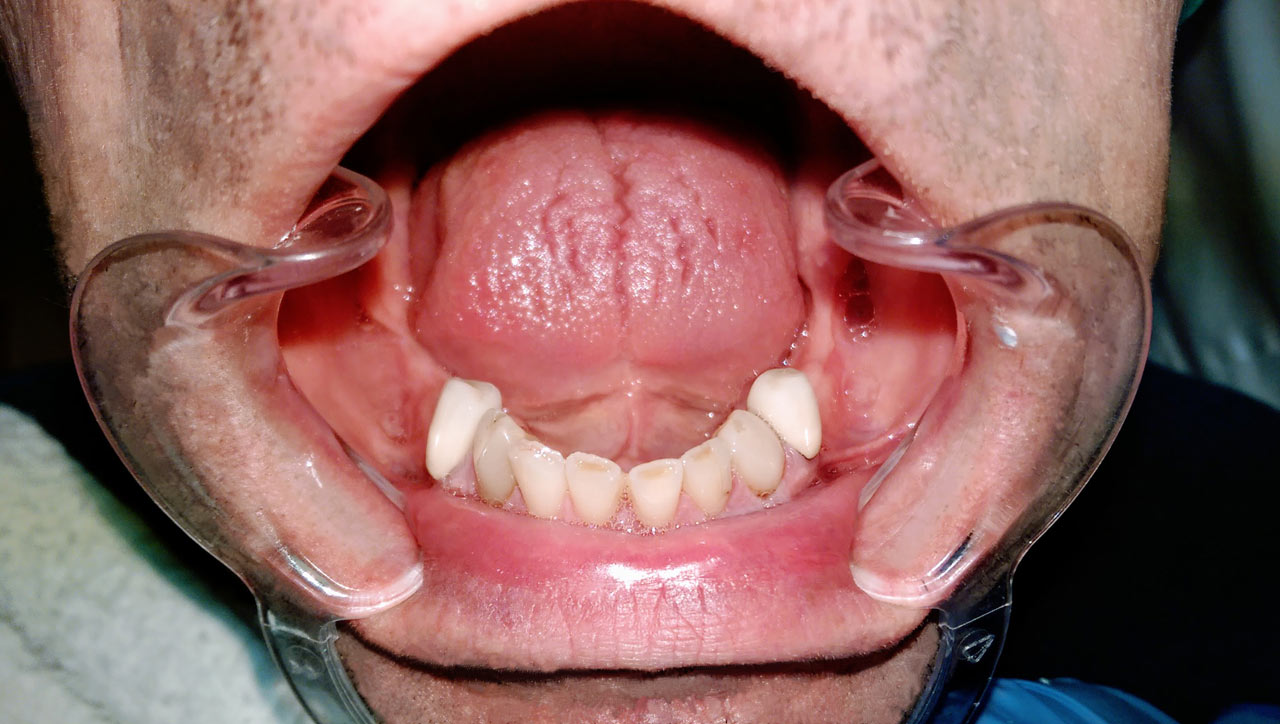

Teljes szájüregi rehabilitáció két lépésben

Ismét egy teljes szájüregi rehabilitáció két lépésben. Először az alsó fogak lettek kihúzva és azonnal implantálva, híddal ellátva, majd később a felső. IHDE svájci azonnal terhelhető implantátumok és cirkónium hidak. Dr. Kelemen Péter és a Symbion Fogtechnika közös munkája.